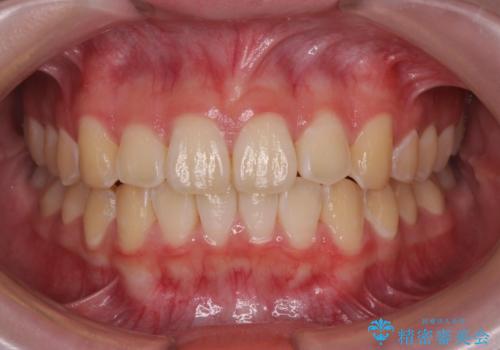

がたつきが無くなり満足して頂けました。

矯正が終わった後は保定装置を使用しないと後戻りしてしまうのでしっかりと保定装置を使用する必要があります。